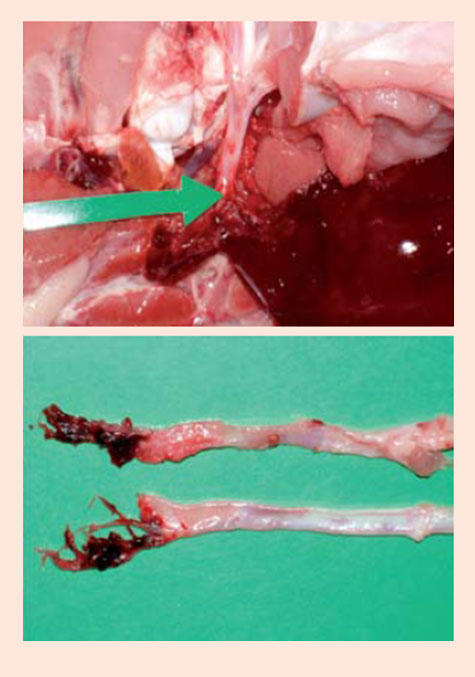

3, 4.- En todos los casos, se observó ruptura unilateral principalmente de la arteria renal izquierda. Después de la separación cuidadosa del parénquima renal, se reveló el extremo roto de la arteria. La causa es desconocida pero algunos factores patogénicos que pueden acompañar son la presión sanguínea alta en pavos, su predisposición natural a la arterioesclerosis y la falta de vasa vasorum intra mural de la aorta descendiente.